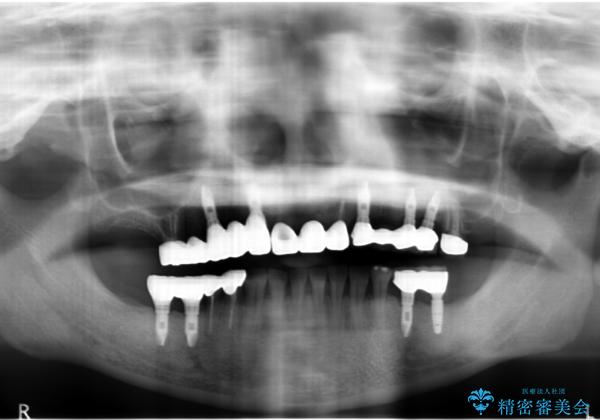

- 痛くて噛めない、これまでだましだまし治療をしてきたがこれを機にすべてきっちりと治したい、口の中の悩みを解決したいと来院されました。

抜歯や歯周病治療、欠損補綴を含め、全顎的な治療を計画・提案します。

(他Drからの引き継ぎ [治療中] の状態より担当)

口腔内に歯の破折や歯周病、虫歯、欠損など複数の問題が存在する場合局所的に問題を解決していくのではなく全顎的な治療を行っていくことで長期的な予後を見込むことができます。